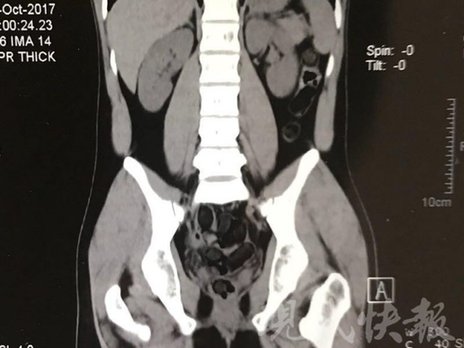

小伙體內(nèi)藏毒300余克 CT掃描圖密密麻麻

運(yùn)毒小伙:希望被判處死刑

由于毒品在體內(nèi)一旦泄露有可能致命,警方第一時(shí)間將阿永帶到醫(yī)院進(jìn)行檢查。CT 掃描的結(jié)果顯示,阿永體內(nèi)布滿了密密麻麻的白色圓柱狀固體,就像一粒粒的蠶蛹。在南京市公安局鼓樓分局二板橋派出所,阿永分四次排出了毒品,毛重369.99克。經(jīng)訊問(wèn),阿永交代了自己全部的犯罪事實(shí)。目前,阿永已被刑事拘留。